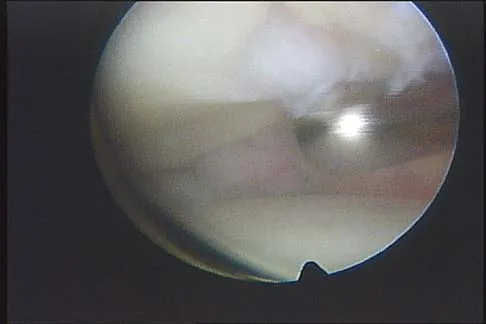

Figure 4a shows the radiograph of a 20-year-old man who has an injury to the right shoulder. Figure 4b shows an arthroscopic view (posterior portal). The arrow points to a

Explanation